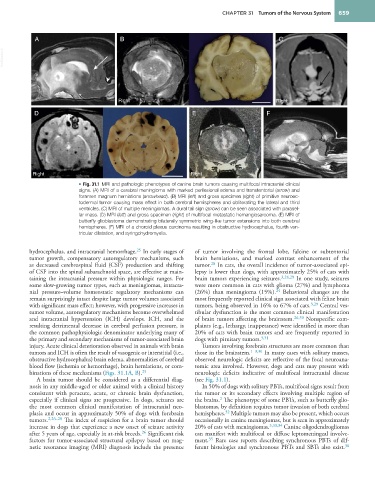

• Fig. 31.1 MRI and pathologic phenotypes of canine brain tumors causing multifocal intracranial clinical

signs. (A) MRI of a cerebral meningioma with marked perilesional edema and transtentorial (arrow) and

foramen magnum herniations (arrowhead). (B) MRI (left) and gross specimen (right) of primitive neuroec-

todermal tumor causing mass effect in both cerebral hemispheres and obliterating the lateral and third

ventricles. (C) MRI of multiple meningiomas. A dural tail sign (arrow) can be seen associated with parasel-

lar mass. (D) MRI (left) and gross specimen (right) of multifocal metastatic hemangiosarcoma. (E) MRI of

butterfly glioblastoma demonstrating bilaterally symmetric wing-like tumor extensions into both cerebral

hemispheres. (F) MRI of a choroid plexus carcinoma resulting in obstructive hydrocephalus, fourth ven-

tricular dilatation, and syringohydromyelia.